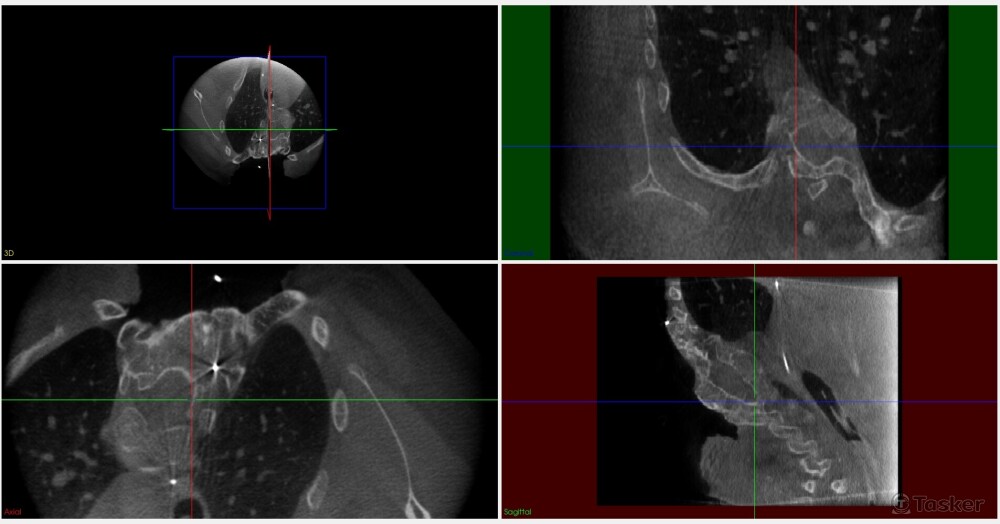

脊椎側彎案例dicom,原始正切視圖